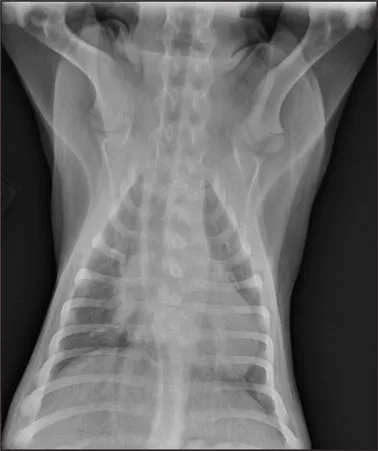

CASE 1.1 A 7-year-old neutered male Labrador Retriever who was hit by a car. You obtain these thoracic radiographs: Figs. 1.1a, b, left and right lateral projections, respectively; Figs. 1.1c, d, ventrodorsal and dorsoventral projections, respectively.

1.1c